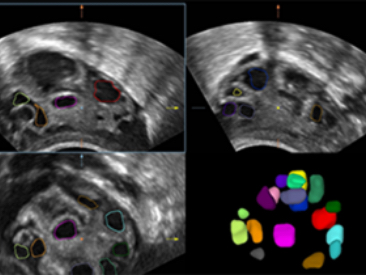

Obrazy kliniczne